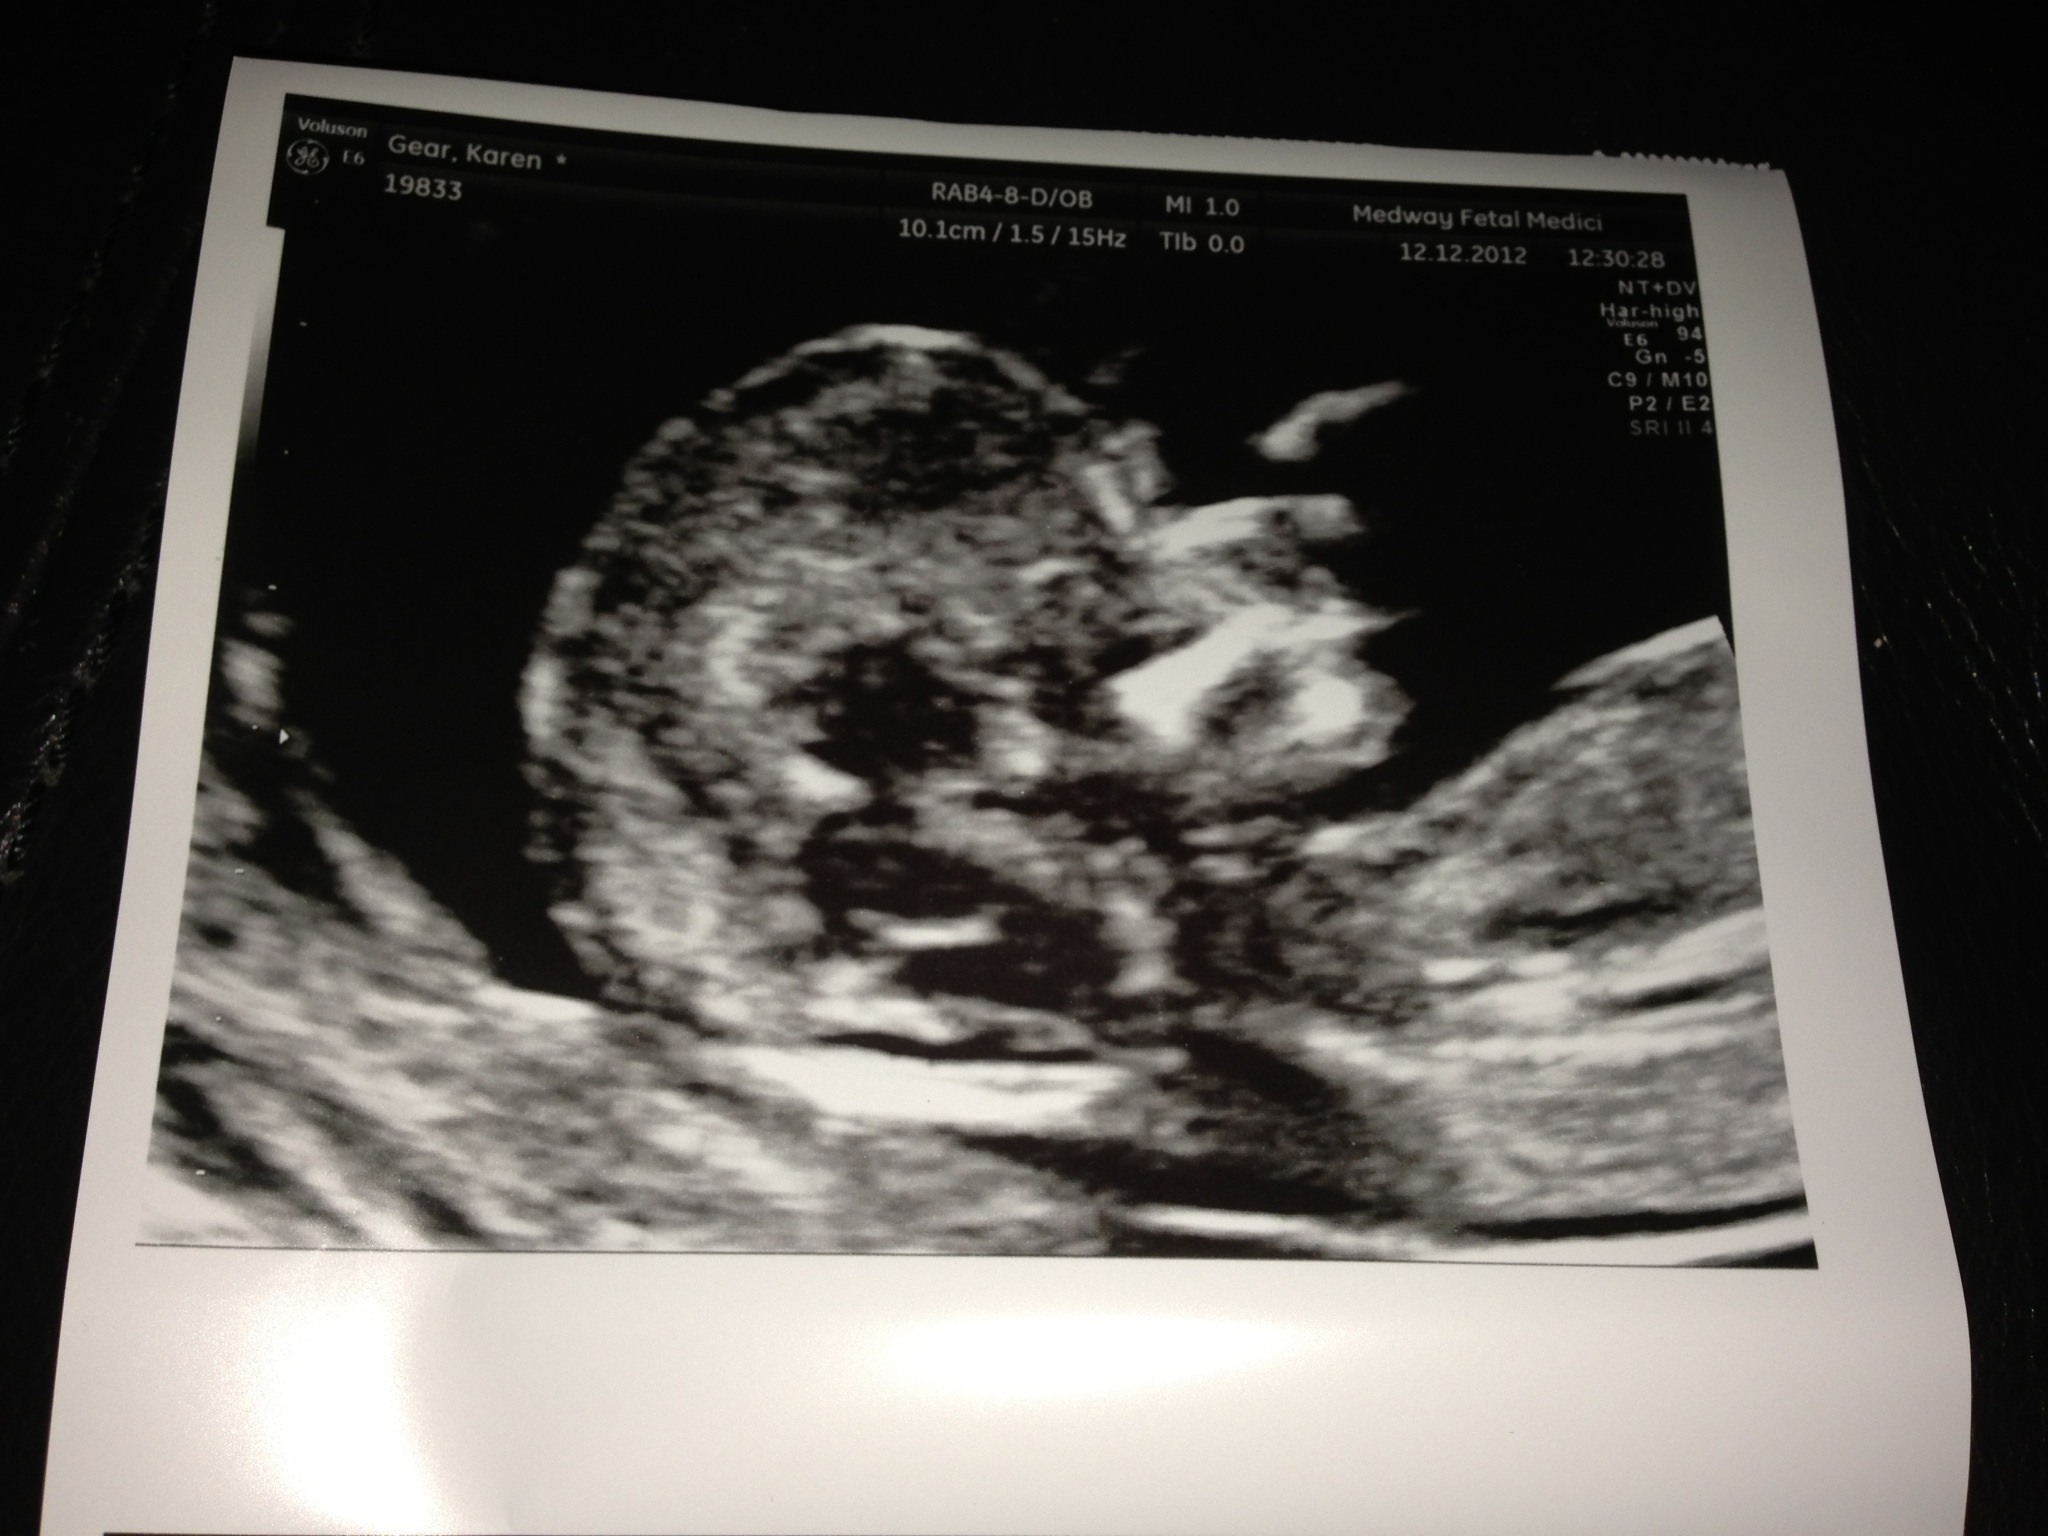

Here are the pics from my phone - I did start a new thread but now can't delete it - getting in a right mess - sorry everyone

Hope these are better??

I cant decide if its nub or cord....something about it looks odd....idk??

Is the sticky up thing a leg then the slight white line the nub? Don't think it's all there though. Is this one any better?? Attachment 7133

Boy definitely. The nub usually appears right on top of the baby's bottom, especially in boys. (Right after the bottom part of the stomach caves in.) The cord in this picture is a little further up.